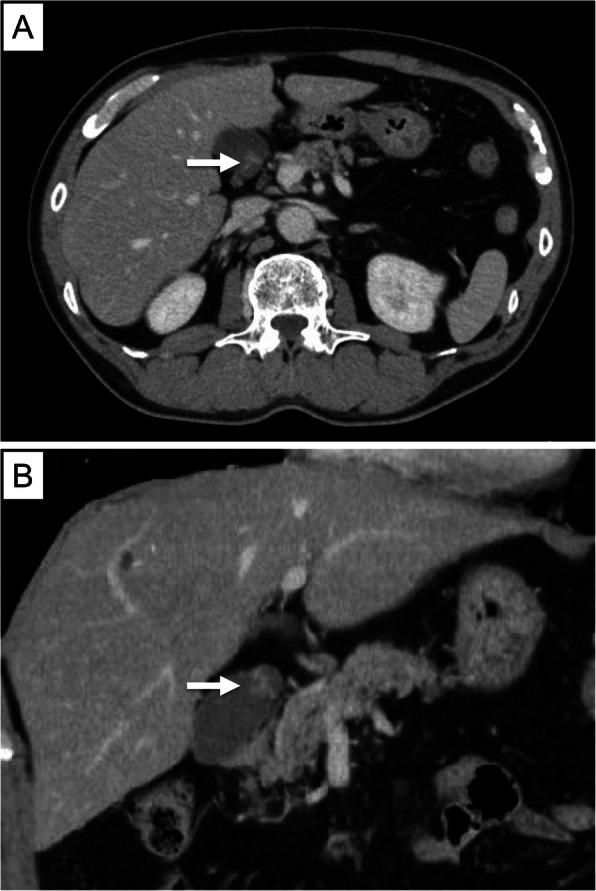

A 10-mm pedunculated polyp in the gallbladder neck was detected on a follow-up abdominal ultrasound in a 60-year-old man with chronic hepatitis and hepatitis B without medication. Six months later, an abdominal ultrasound revealed that the tumor had enlarged to 12 mm in size. He was asymptomatic and had no abnormalities in other laboratory examinations, including the tumor markers, carcinoembryonic antigen and CA19-9. Abdominal ultrasound showed a 12-mm polyp in the neck of the gallbladder with perfusion and focal thickening of the gallbladder wall. A gallbladder stone was also seen in the fundus. An enhanced computed tomography scan and magnetic resonance imaging revealed a polypoid lesion and gallbladder stone located at the neck of the gallbladder and the fundus, respectively. Malignancy could not be excluded, and hence, a laparoscopic cholecystectomy was performed. Pathologically, a pedunculated polyp (14 × 11 × 15 mm) was observed in the neck of the gallbladder, and the polypoid lesion comprised nests or trabecular growths of clear NET cells in the lamina propria (ENETS: T1N0M0; AJCC: T1aN0M0). Immunohistochemical staining with synaptophysin, chromogranin A, and CD56 was confined to the tumor. The pathological diagnosis was clear cell NET G1 of the gallbladder. Although clear cell NET is often described as a distinct manifestation of von Hippel-Lindau disease (VHL), the patient had no past medical or family history of VHL. Until his one-and-a-half-year follow-up, the patient was doing well and without any signs of recurrence.

一名60岁患有慢性肝炎和乙肝且未接受药物治疗的男性,在腹部超声随访检查中发现胆囊颈部有一个10毫米带蒂息肉。六个月后,腹部超声显示肿瘤增大至12毫米。他没有症状,其他实验室检查包括肿瘤标志物癌胚抗原和CA19-9均无异常。腹部超声显示胆囊颈部有一个12毫米息肉,伴有胆囊壁灌注和局部增厚。在胆囊底部还发现了一枚胆囊结石。增强计算机断层扫描和磁共振成像显示,息肉样病变和胆囊结石分别位于胆囊颈部和底部。无法排除恶性可能,因此进行了腹腔镜胆囊切除术。病理检查发现,在胆囊颈部观察到一个带蒂息肉(14×11×15毫米),息肉样病变由固有层中透明NET细胞的巢状或小梁状生长构成(ENETS:T1N0M0;AJCC:T1aN0M0)。突触素、嗜铬粒蛋白A和CD56的免疫组化染色局限于肿瘤。病理诊断为胆囊透明细胞NET G1。尽管透明细胞NET常被描述为冯·希佩尔-林道病(VHL)的一种独特表现,但该患者既往无VHL病史或家族史。截至他的一年半随访时,患者情况良好,无任何复发迹象。